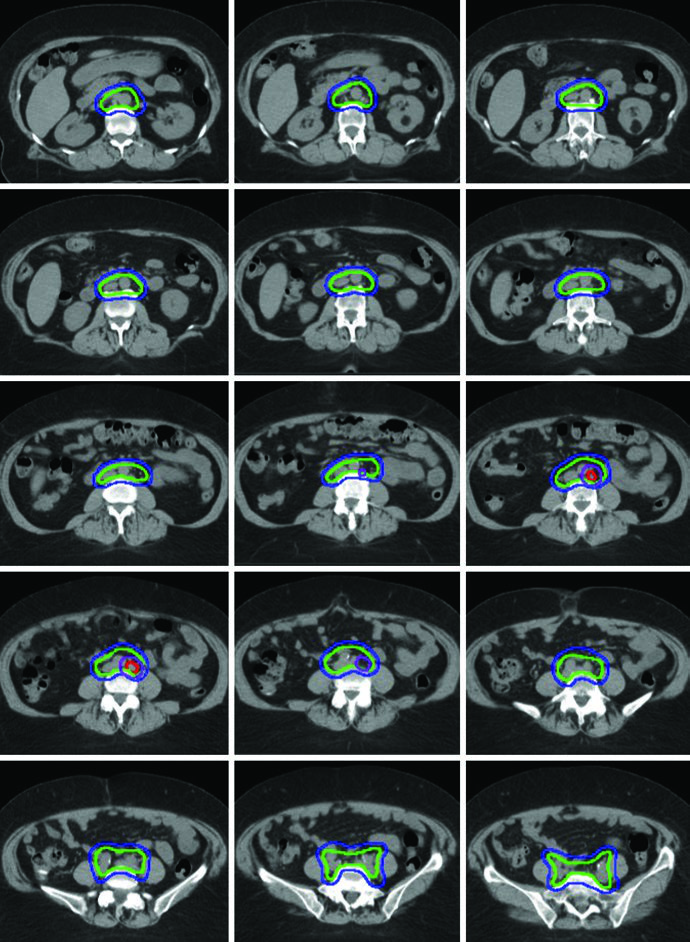

Campos Estendidos e Boost com SIB

A radioterapia de campo estendido é frequentemente indicada quando há envolvimento patológico de linfonodos para-aórticos ou ilíacos comuns altos. Nesses casos, o limite superior do CTV3 pode se estender ao interespaço T12-L1 ou L1-L2, ou à vasculatura renal. Campos estendidos modificados com limites superiores entre L4-L5 e L1-L2 podem ser utilizados em pacientes com envolvimento nodal pélvico extenso ou de ilíacas comuns altas.

Um boost de 5 a 15 Gy pode ser adicionado para doença nodal bruta ou envolvimento parametrial. Esse boost pode ser administrado de forma sequencial ou como boost integrado simultâneo (SIB). O livro ilustra um caso de adenocarcinoma endometrioide estádio IB, pós-histerectomia laparoscópica assistida por robô, em que um linfonodo para-aórtico aumentado foi encontrado na simulação. A paciente foi tratada com IMRT de campo estendido usando técnica ITV. O limite superior do CTV3 foi modificado para incluir o hilo renal, o GTV da doença nodal bruta foi contornado e recebeu SIB de 5940 cGy com 4760 cGy em 28 frações para os demais linfonodos.

Essa abordagem de SIB permite tratar o volume nodal macroscópico com dose escalada sem adicionar frações extras ao curso do tratamento. Na prática clínica, a escolha entre SIB e boost sequencial depende da geometria do caso e das restrições de dose nos órgãos de risco adjacentes. Para estratégias complementares na radioterapia ginecológica definitiva com IMRT, confira o artigo dedicado.